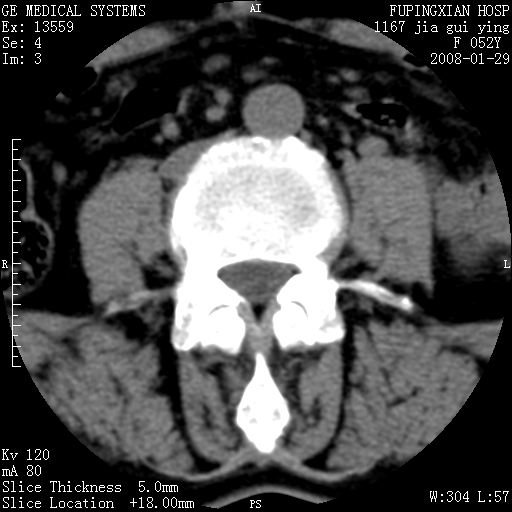

以下是引用dyqct在2008-1-29 21:49:00的发言:[br]考虑:1、腰4-5椎间盘突出(左椎间孔外侧型)。[br] 2、硬膜囊内钙化,多考虑蛛网膜炎所致粘连钙化,请询问病史病人以往做过碘油造影吗?

以下是引用liuyue在2008-1-30 4:32:00的发言:[br]1. 腰4-5椎间盘突出。[br]2. 硬膜囊内钙化,考虑a.蛛网膜炎所致粘连钙化;[br] b.硬膜囊内血管畸形.[br] c脊髓纵裂畸形.[br] 另:询问病史病人以往做过碘油造影吗?